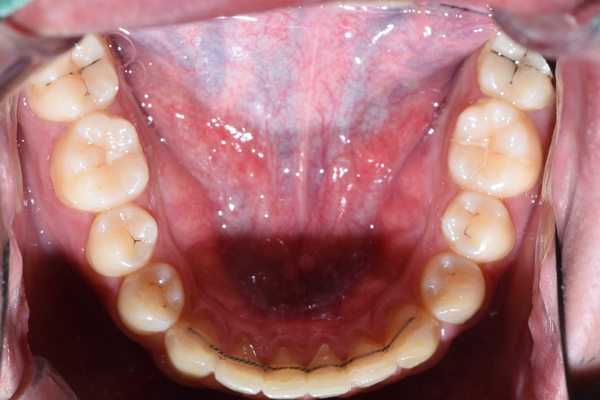

어금니도 씹는면도 썩어있었지만 어금니의 옆면도 많이 썩어있었습니다.